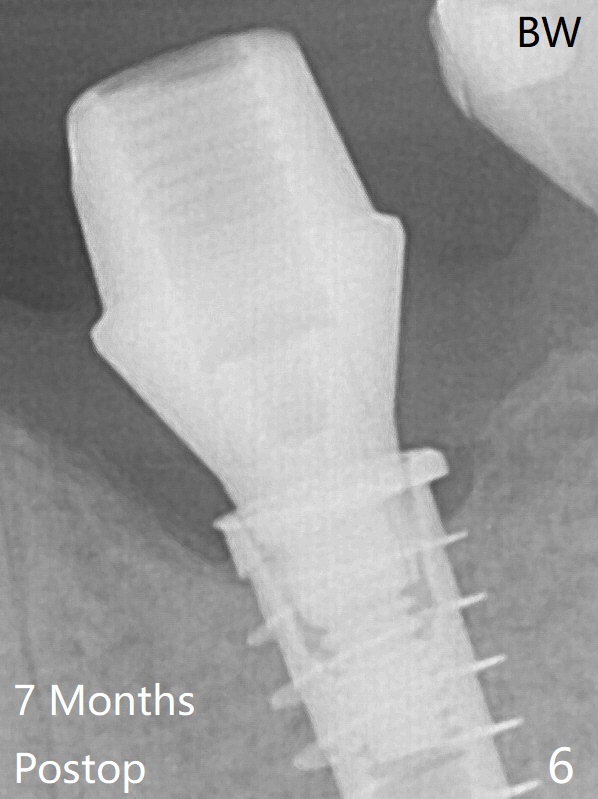

Due to the narrow ridge, a 4.5x11 mm implant is placed (Fig.4); before as well as after placement of a 6x4(3) mm abutment, the mesial socket (*) is filled with Vera graft and autogenous bone as well as collagen plug.  Following suturing, periodontal dressing is applied to the wound.  There is no apparent bone loss 7 months postop (Fig.6 (BW: bitewing)) or 14 months post cementation (Fig.7).  In fact the abutment has been incompletely seated, which may be related to #13 failure.

The bone density of the crest appears to increase with function.